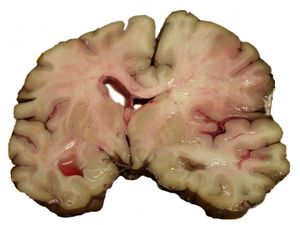

نزيف المخ الداخلي

النزفي